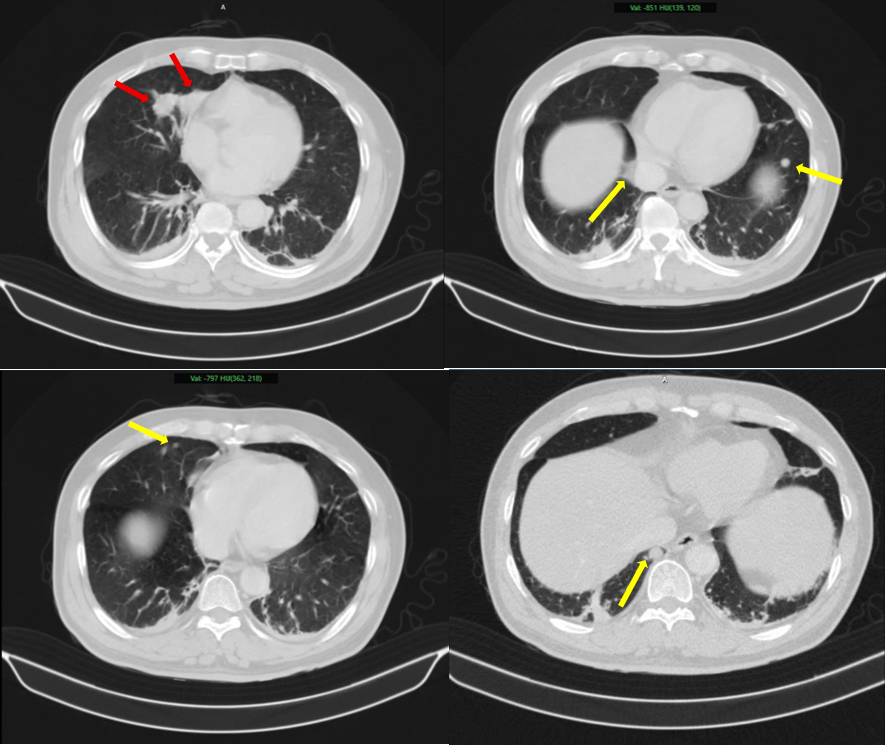

Bệnh nhân nam, 63 tuổi, nhập viện trong tình trạng tiểu khó kéo dài. Qua thăm khám và thực hiện các kỹ thuật cận lâm sàng như chụp cắt lớp vi tính (CT), cộng hưởng từ (MRI), xạ hình xương và đặc biệt là PET/CT, các bác sĩ phát hiện tổn thương tại tuyến tiền liệt cùng nhiều khối u ở phổi, tuyến thượng thận và xương.

Thách thức lớn nhất trong trường hợp này là xác định bản chất các tổn thương: đâu là khối u nguyên phát, đâu là di căn. Nếu chẩn đoán không chính xác, việc lựa chọn phương pháp điều trị có thể sai lệch, ảnh hưởng trực tiếp đến hiệu quả điều trị.

Kết quả sinh thiết và phân tích mô bệnh học kết hợp hóa mô miễn dịch đã giúp làm rõ: khối u phổi là ung thư biểu mô tuyến của phổi, trong khi khối u tuyến tiền liệt là ung thư biểu mô tuyến với điểm Gleason 9 - thuộc nhóm nguy cơ cao. Hai loại ung thư này có nguồn gốc hoàn toàn khác nhau, không phải di căn chéo.